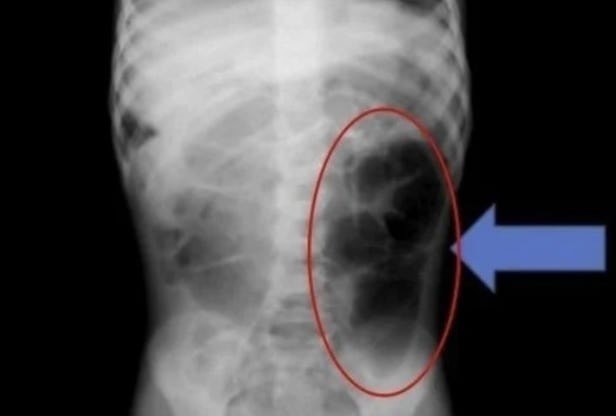

Các bác sĩ đã phát hiện ra búi tóc rối bên trong dạ dày của một bé gái 6 tuổi bị đau bụng và gặp các vấn đề về tiêu hóa.

Ngày 20/1, tạp chí y khoa Cureus đã đăng tải trường hợp của một bé gái 6 tuổi, tên A, sống tại Ả Rập Xê Út. Bé A đến bệnh viện vì đột nhiên bị đau bụng và các vấn đề về tiêu hóa. Sau khi thăm khám, các bác sĩ xác nhận có một búi tóc rối bên trong dạ dày của bé.

Nhóm y tế phát hiện ra rằng sợi tóc không chỉ nằm trong dạ dày mà còn lan đến ruột non. Họ cho biết: "Nếu bệnh nhi có các triệu chứng dai dẳng như đau bụng tái phát, nôn mửa hoặc chán ăn kéo dài, cần phải xem xét khả năng có dị vật trong đường tiêu hóa".

Búi tóc được phát hiện trong bụng bé gái.